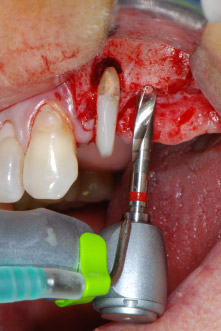

Implantatmotor

Abb. 8: Der nächste Schritt ist die rotierende Präparation des Implantatbetts bis kurz unterhalb des Sinusbodens an Position 25, die mit einem weiterentwickelten Implantatmotor erfolgte.

Im folgenden Schritt wurde das jeweilige Implantatbett an den Positionen 25 und 26 mit rotierenden Instrumenten in einem Winkelstück mit einem Übersetzungsverhältnis von 20:1 (WS-75 L G, W&H) und einem vor Kurzem aktualisierten leistungsstarken Implantatmotor präpariert (Implantmed, W&H) (Abb. 8 und 19).

Die Abschlusspräparation am Sinus erfolgte wieder mit einem piezochirurgischen Instrument.